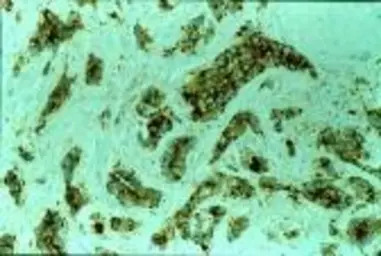

Formalin fixed paraffin embedded human breast carcinoma stained with LRP/MVP antibody (GTX22376).

IHC Image using GTX22376 - Detection of MVP by IHC in Human Breast Carcinoma